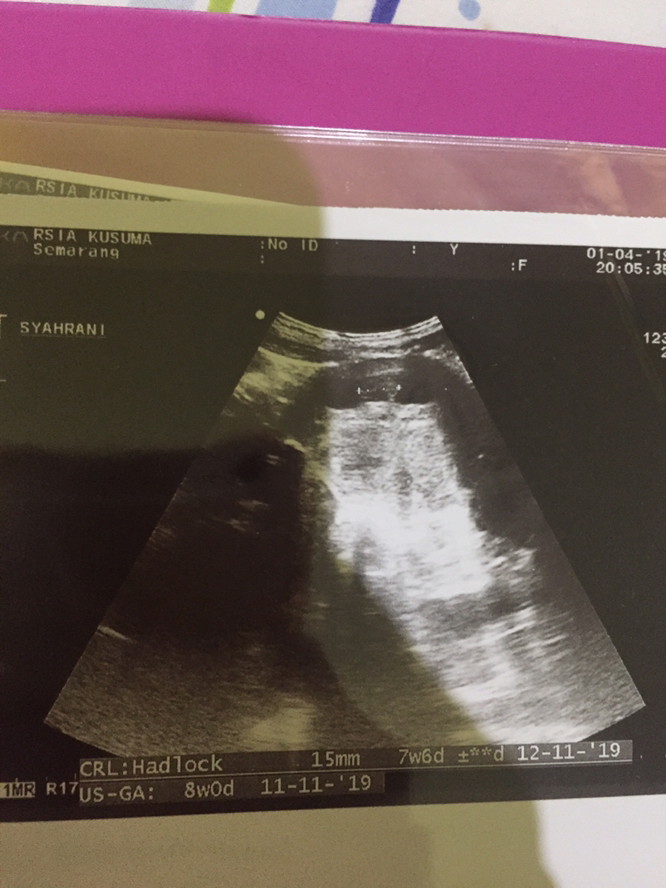

6w apakah masih kantong

bun mau tanya, perkiraan kan ini 6 minggu, masih kantong belum ada titik putih, apakah memang di usia segini belum muncul? mohon infonyaaaa ??

aku dulu masuk 8 weeks baru keliatan ada yolksac nya bund, wajar kok awal2 msh kantung doang

sama aq 6w5d juga blm kliatan baka janinnya , cuman kantong yg terlihat

6w masih wajar Bun,,,cukupin asupan nutrisi nya yaa biar calon debay nya segera kelihatan Bun

yaa bund baru kantung nanti 7 minggu udh ada djj 9 week udh kayak kacang merah bunda

Tggu 2mggu lagi usg bun. Biasanya 8w udh kliatan udah ada dtk jntungnya juga .semagy

Gapapa bun..wajar..nanti juga keliatan..saya 7w keliatan dan kedengeran djj nya